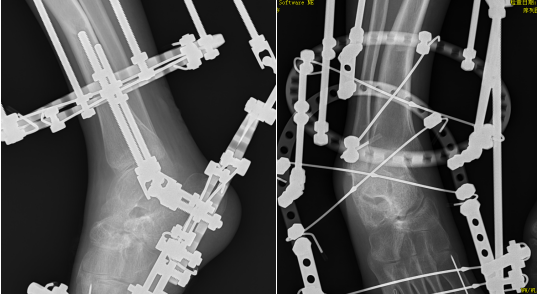

近日,我院骨科中心一区为一位右足部严重内翻畸形伴右足部慢骨髓炎患者实施“右足部畸形llizarov外固定架矫形固定+右足部骨髓炎刮除骨髓泥植入+阔筋膜松解+右足1-4趾肌腱松解克氏针内固定术”。患者术后恢复良好,患肢功能恢复良好,填补了我院llizarov外固定架治疗下肢畸形及骨髓炎的空白,为我院骨科在治疗慢性骨髓炎及四肢畸形方面提供了一种全新的治疗方案。

(术前DR及CT检查示:右足严重内翻畸形,右足第5趾骨及跖骨骨感染)

(术后第1天,足部畸形基本纠正)

(术后2个月,踝关节活动范围明显改善,足底可以正常着地)